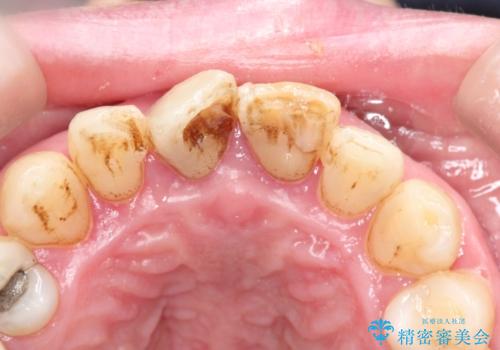

- かけてしまった前歯をきれいにしたいとのことで来院されました。

レントゲンを撮影すると、根の神経の治療が必要なことがわかりました。

根管治療を行いセラミックを装着する計画としました。

ホワイトニングをセラミックを装着する前に行うことで、白くなった周りの歯に合わせたセラミッククラウンを装着することができました。